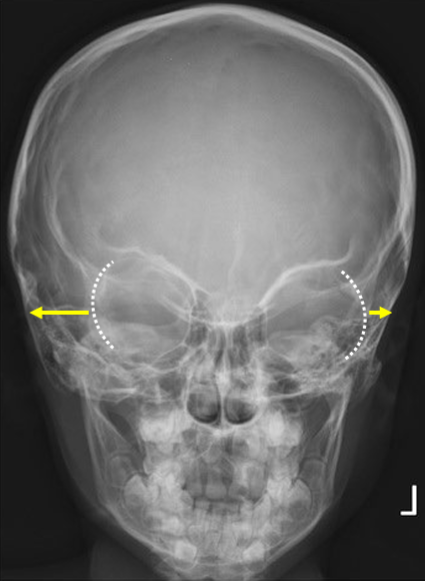

Critique - AP Axial (Towne)

BTP: dorsum sellae and clinoids visualized in the foramen magnum

excessive = SI of the posterior arch of C1 over dorsum sellae

insufficient = dorsum sellae seen superior to the foramen magnum

Tilt: nasal septum and sagittal suture // LA, petrous ridges // SA

Rotation: dorsum sellae equidistant to the lateral borders of the foramen magnum (rotation is towards the narrowed side)